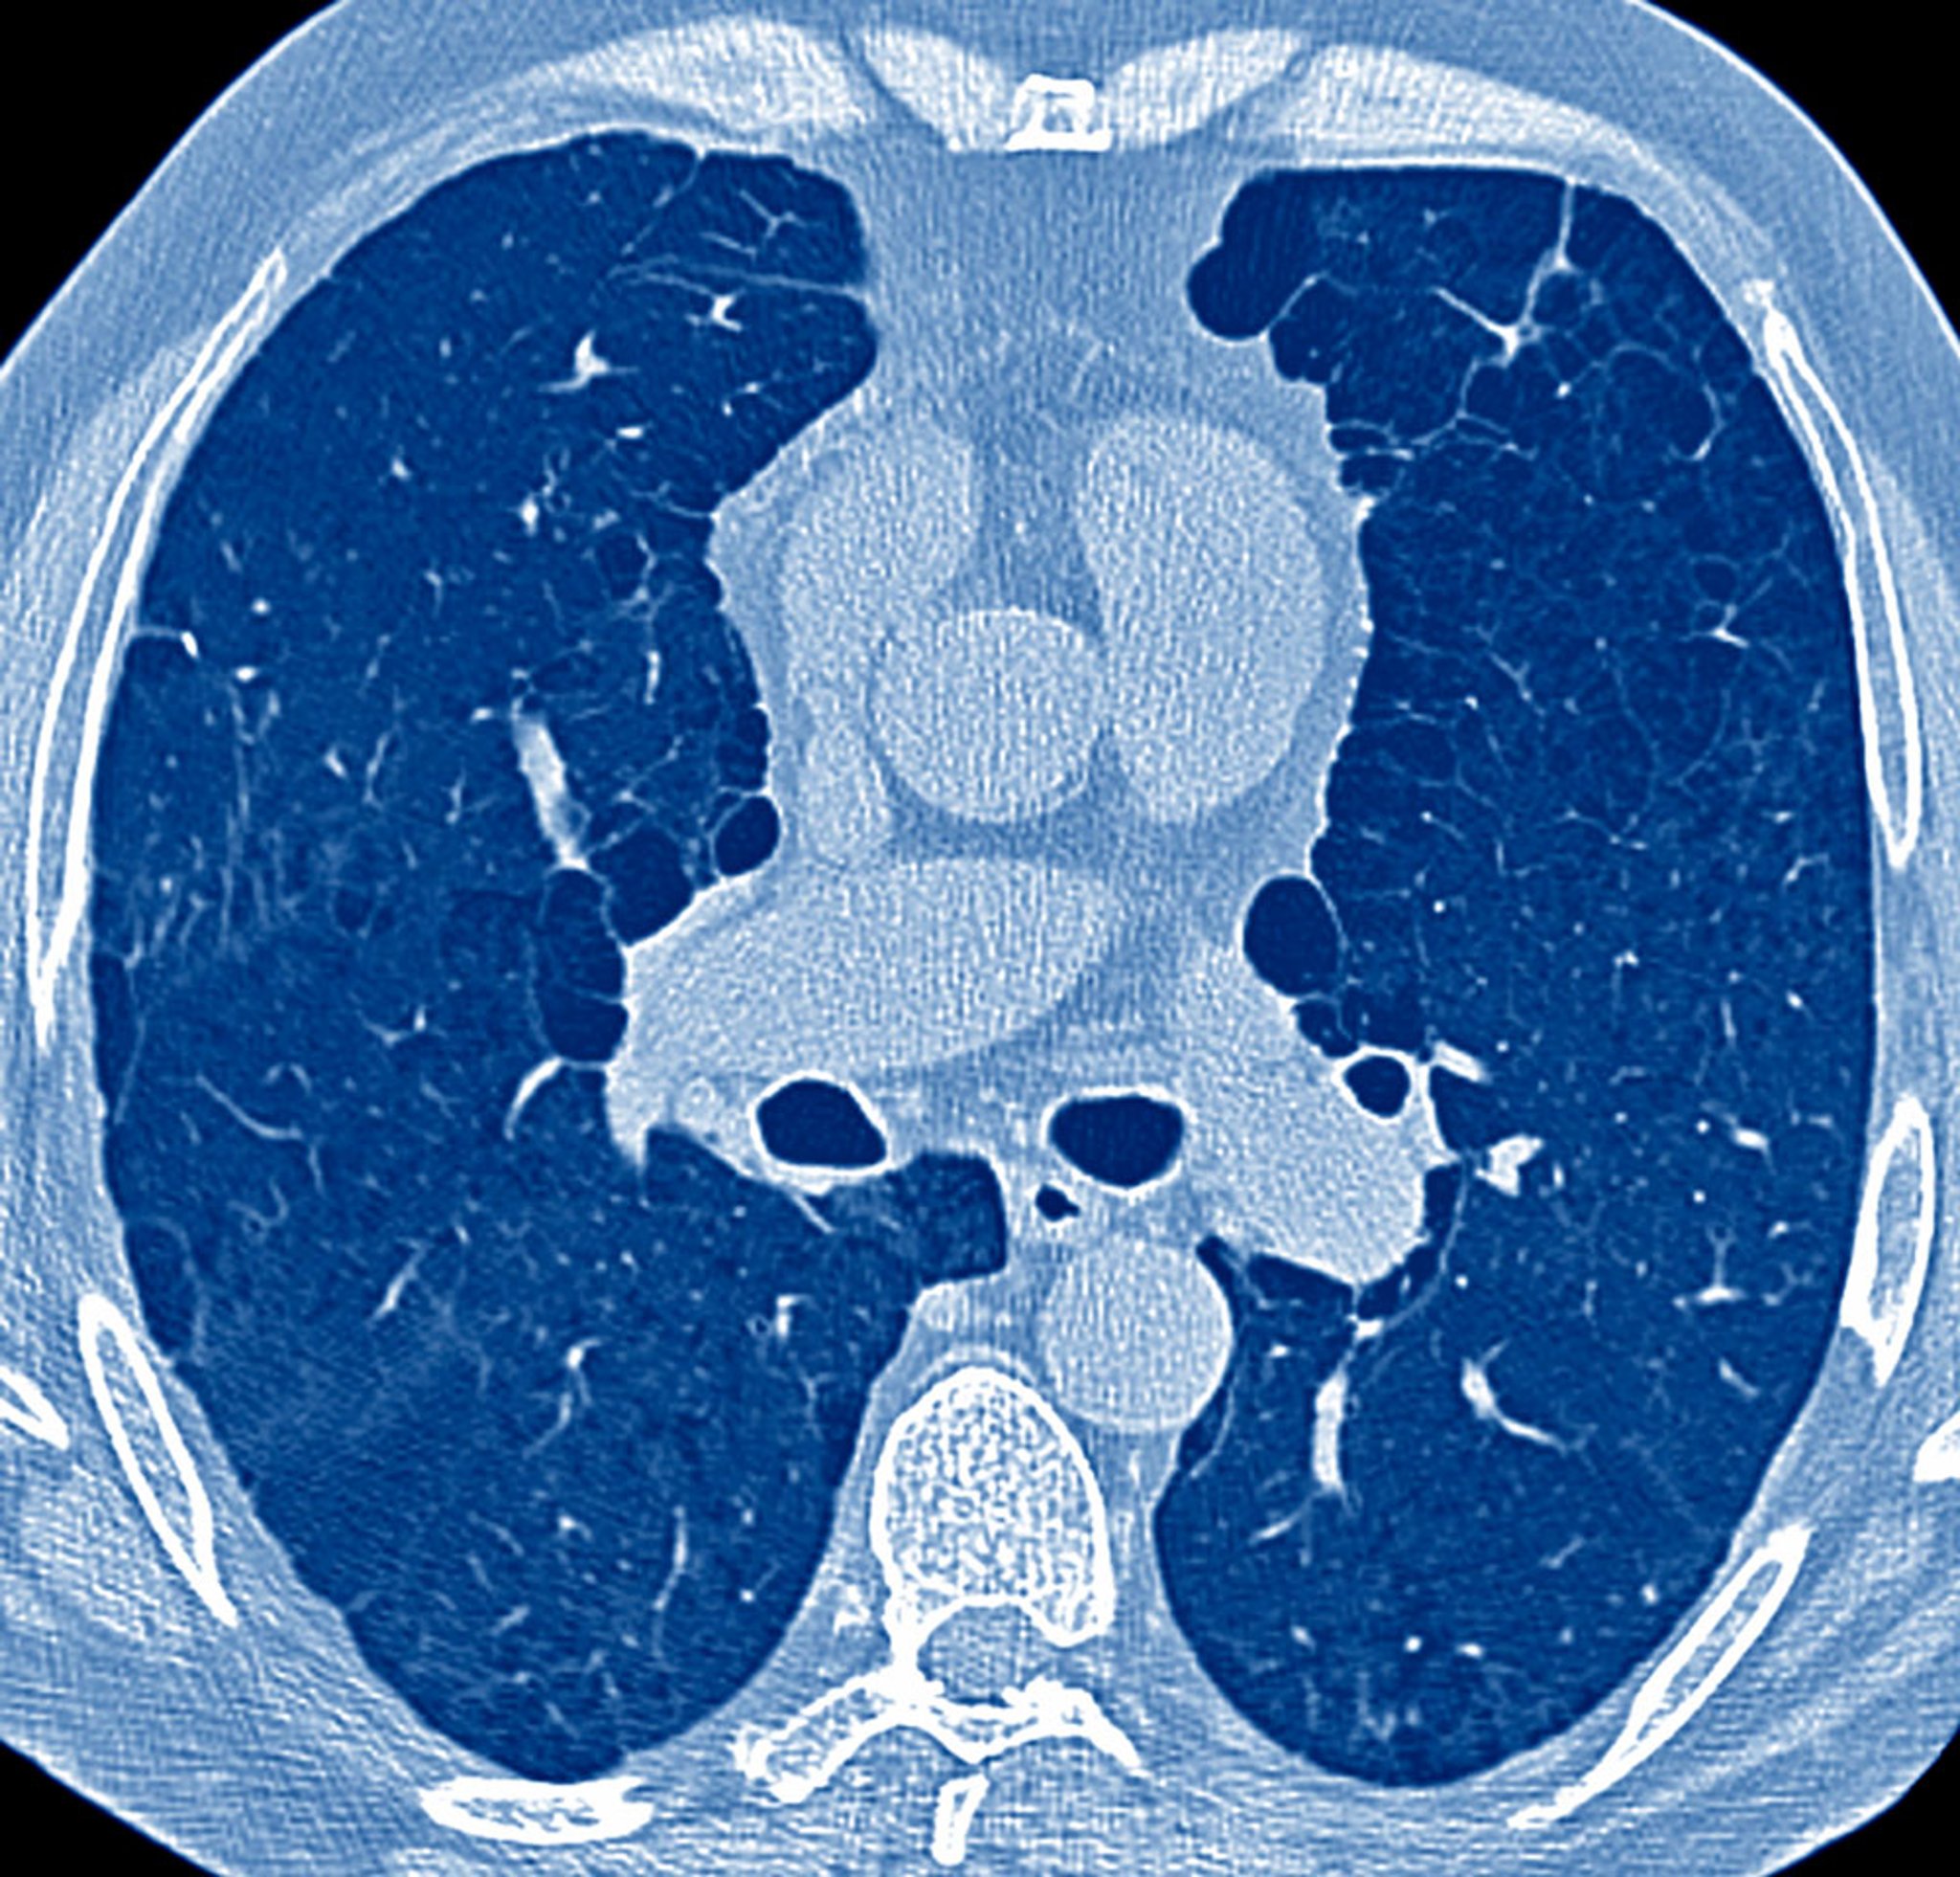

Key components in the evaluation of patients with pulmonary symptoms are the history, physical examination, and, in many cases, a chest radiograph. These components establish the need for subsequent testing, which may include pulmonary function testing, arterial blood gas (ABG) analysis, chest CT and other chest imaging tests, echocardiography, 6-minute walk test, cardiopulmonary exercise testing, right heart catheterization, bronchoscopy, and lung biopsy.